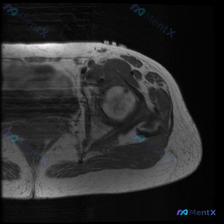

患者提示有髋部软组织积液,单张T1 MRI却没看到异常?这个矛盾怎么解

影像阅片结果

- 骨骼结构:股骨头形态圆整,骨皮质轮廓完整,未见明显骨质中断;股骨头及近端股骨骨髓信号呈中等偏高,符合正常T1加权像骨髓脂肪信号表现,没有局灶性异常低信号。

- 关节结构:髋关节间隙清晰,对位关系良好,未见半脱位;股骨头形态正常,无塌陷、畸形,盂唇结构因单幅图像限制显示一般,未见明确撕裂或异常囊肿信号。

- 周围软组织:盆腔周围肌群轮廓清晰,信号均匀,未见异常软组织肿块;肌肉体积对称,肌腱附着点未见明显水肿或异常信号;未发现明确的骨膜反应、关节囊积液或肌肉水肿征象。

最终影像结论:本次单张T1序列未见明确骨质、关节、软组织异常病变。